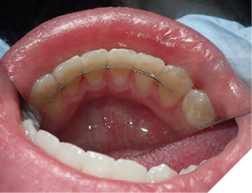

Fig. 1A

Fig. 1B

Fig. 1C

The majority of the orthodontic practices offer a period of “supervised retention” to their patients and communicates the customized retention recommendation with the patient’s general dentists. It is extremely important to work as a team to achieve long term clinical success in maintaining a functional bite and aesthetic smile. The general dentists continue to see their patients on a regular basis and have an opportunity to assess the orthodontic retainers and the bite after the supervised retention period is completed by the orthodontists. With great care, orthodontic retainers would serve for a long time (Fig. 1) without any major issues. However, in some cases, the failure to notice the clinical problems early on results in functional issues that would require a comprehensive orthodontic treatment to correct it (Fig. 2).